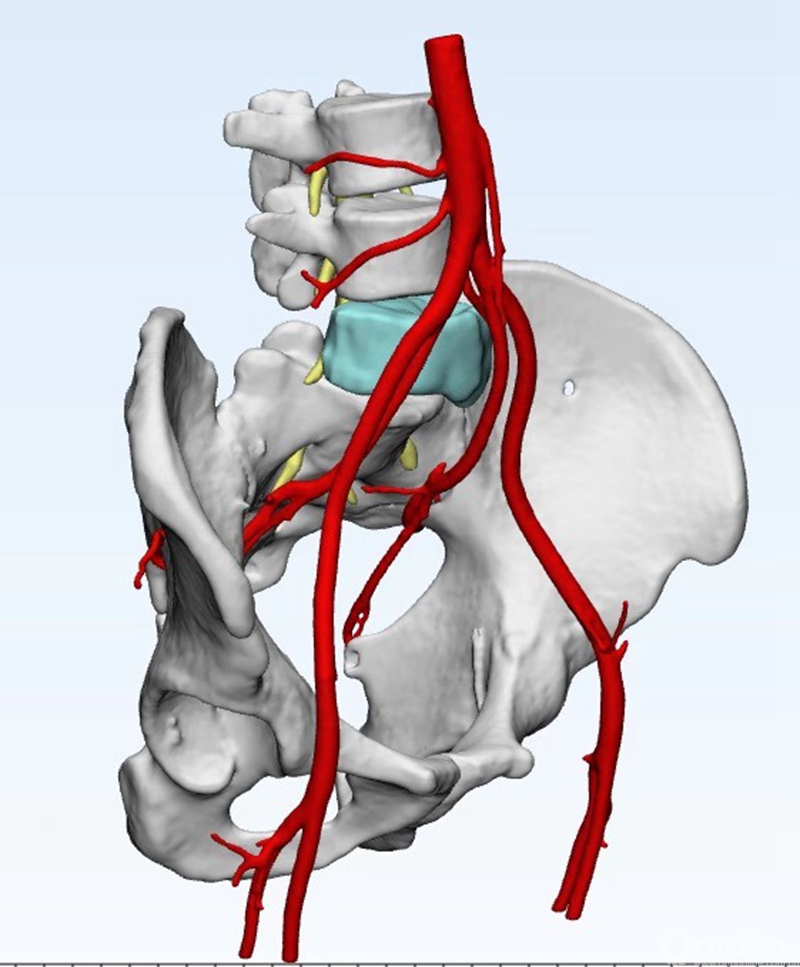

术前CT三维重建